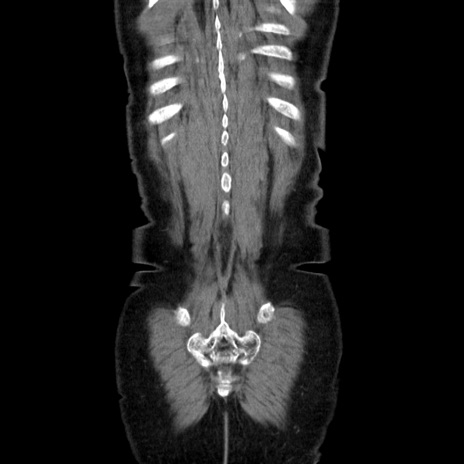

症例5(冠状断像)

【症例】70歳代女性

【主訴】お腹が張る

【現病歴】1週間くらい前から腹部膨満の自覚あり。昨日夜から増悪したため、本日救急外来受診。

【身体所見】意識清明、BT 36.5℃、BP 165/106mmHg、HR 80bpm、SpO2 98%、腹部:膨満、軟、自発痛・圧痛なし、触診にて不快感あり、腸蠕動音:減弱

【データ】WBC 12600、CRP 1.04